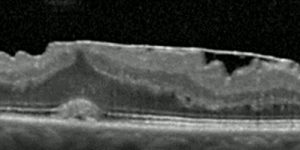

epiretinal-membran

• epiretinal-membran